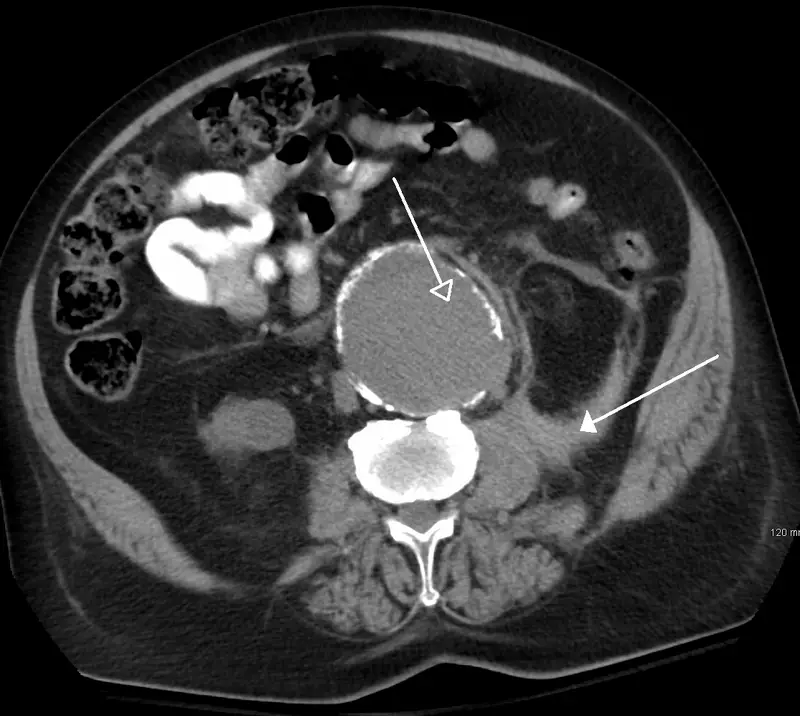

Abdominal Aortic Aneurysm

Abdominal aortic aneurysm (AAA) is an aneurysm of the abdominal aorta.

Abdominal aortic aneurysm typically develops above the aortic bifurcation but below the renal arteries.

Abdominal aortic aneurysm (AAA) is typically associated with hypertension and atherosclerosis.

Abdominal aortic aneurysm (AAA) typically presents with a triad of:

- Flank pain

- Pulsating abdominal mass

- Hypotension

Symptoms of abdominal aortic aneurysm include an abdomen lump that pulses initially and enlarges over time.

Complications of abdominal aortic aneurysm (AAA) include:

- Rupture, especially when the diameter is greater than 5 cm

- Compression of nearby structures (such as the ureter)

- Thrombosis

- Embolism